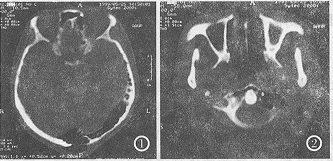

CT检查 头部CT平扫,左侧颞骨鳞部、颧突、乳突及岩锥见过度气化。气化扩展至同侧枕骨中下部并越过中线,在中线处形成2cm×3cm骨缺损,气体溢于皮下(图1)。向下延伸至枕骨大孔周围。环椎左侧侧块,前弓亦见气房(图2)。上述低密度影CT值为-786~964.7HU。

图1 头部CT平扫,骨窗示左颞骨、枕骨气化,并越过中线累及枕骨右侧。在中线处见局部骨缺损,气体经该处溢于皮下,形成含气肿块。

图2 颈部CT轴位平扫,示环椎左侧侧块及前弓亦有气化。